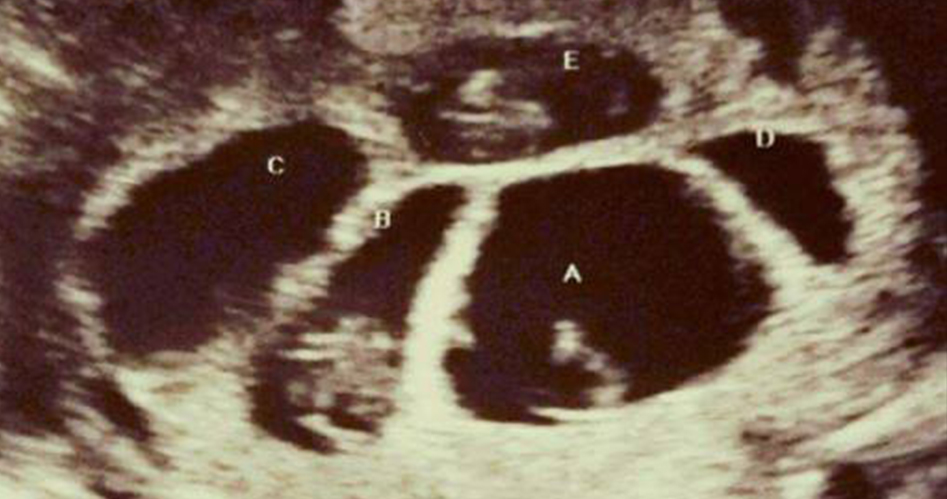

透過超音波畫面可以看到,布萊安娜肚子裡竟然出現五個胎兒!

之前一直不懷孕,沒想到一來就是五個,戲劇性的變化讓她相當震撼「我是真的差點昏 倒!」

「我當時震 驚到說不出話,就做在那裡呆瞪著螢幕,完全不敢相信。我真的不知道我可以一次懷上五個寶寶。」

雖然曾出現過不少多胞胎的案例,但實際上來說,懷上三胞胎的機率低於5%,而像布萊安娜這樣的五胞胎,機率更是只有5千萬分之一!